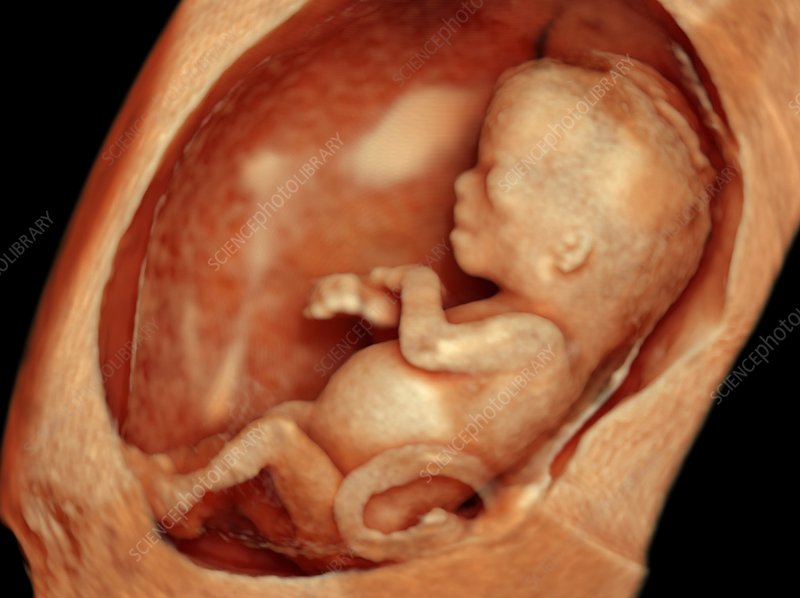

- 9-12. haftalarda dış genital organlar belirginleşmeye başlar.

- Ultrasonla net olarak ayırt edilebilmesi genellikle 18-21. haftalarda mümkün olur.